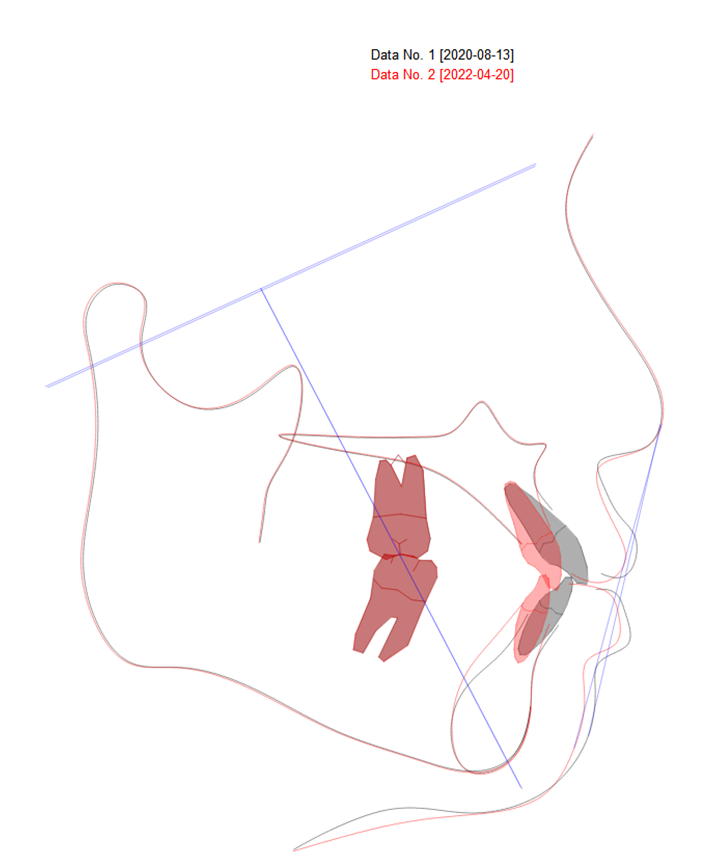

골격 사진을 분석해보면 단안모에 약간의 돌출감이 있는 것을 확인할 수 있었어요. 하지만 E-plane에 대해 윗입술과 아랫입술의 돌출은 심하지 않았기 때문에 비발치 치료로 공간을 폐쇄하고 튀어나온 전치부 각도를 수정하는 정도로 교정을 하기로 환자분과 상담을 했어요.

부가적으로 E-plane이란 용어를 잠시 설명 드리자면 코 끝과 턱끝을 이은 선을 말하는 것인데요. 골격적 특성에 따라 부차적으로 설명드릴 것이 많긴 하지만 흔히 교정과에서 이 선을 기준으로 입술의 돌출도를 즉각적으로 확인을 하는 편입니다.

중첩된 골격 사진을 보시면 윗니와 아랫니의 공간을 이용해서 돌출된 치아와 입술을 해결하였습니다.